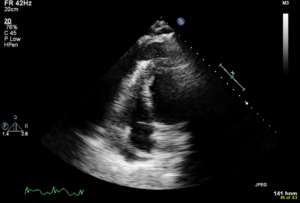

A 52-year old man with a history of diffuse large B cell lymphoma in remission presented with 3 weeks of shortness of breath, cough, fever, and shock. Electrocardiogram revealed sinus tachycardia, diffuse ST segment elevations, PR segment depression, prolonged QTc, and electrical alternans. Bedside echocardiogram was performed, revealing a large circumferential pericardial effusion with tamponade physiology. The patient underwent echo-guided pericardiocentesis with drainage of 400 ml of purulent fluid. Pericardial and blood cultures were positive for Haemophilus influenzae. A CT of the chest was indicative of empyema. Given the patient’s history of rituximab use, autologous stem cell transplant, and profound infection, immunoglobulin levels were drawn and found to be undetectable. The patient received 6 weeks of intravenous antibiotics with IVIG infusions. He was treated with colchicine and aspirin for purulent pericarditis. Two months later, a cardiac MRI was performed, which revealed resolution of the pericardial effusion. No evidence of constrictive pericarditis was noted on MRI, but continued pericardial enhancement was observed. Colchicine was continued for an additional 3 months. The patient made a full recovery at 6 month follow up.

In developed countries, purulent pericarditis is rare, accounting for less than 1% of cases of pericarditis.1 Risk factors for development of bacteria pericarditis include bacteremia, immunocompromised state, and thoracic surgery.2 While gram positive organisms (primarily Staphylococcus aureus and Streptococcus pneumoniae) are the most common organisms causing purulent pericarditis, infection with gram negative organisms such as Haemophilus influenzae remains very rare.3 Only 9 cases of purulent pericarditis secondary to Haemophilus influenzae have been reported in the literature.4 The patient in this case developed septic shock due to an acquired immunodeficiency from treatment with rituximab for lymphoma 7 years prior, resulting in permanent loss in immunoglobulin production by B cells. As in this case, direct extension from pneumonia or empyema are frequent routes of infection into the pericardial space. Pericardiocentesis is indicated if there is a suspicion of bacterial infection as purulent pericarditis carries a 30% mortality rate. Bedside echocardiography played a critical role in the evaluation of pericardial tamponade and prompt treatment with pericardiocentesis, resulting in an excellent patient outcome in this case.